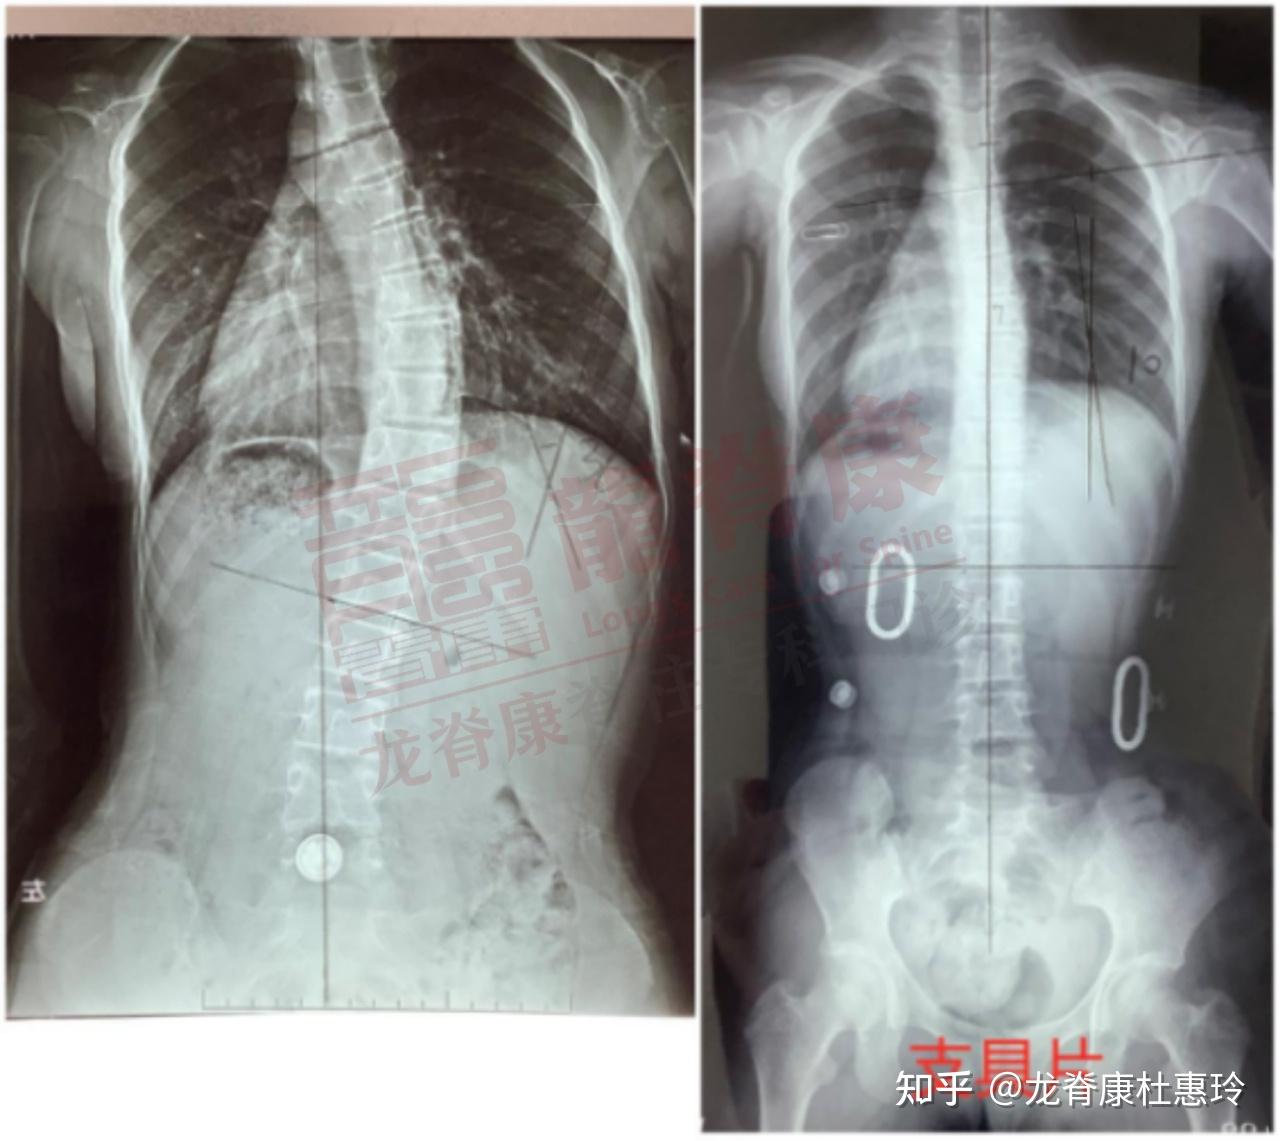

超过30度的脊柱侧弯,怎么改善? - 知乎

脊椎侧弯30度

侧弯超过30度的成年患者还能否逆袭

脊柱侧弯

手术40度以上的手术功能性脊柱侧凸:30度以下的支具,训练结构性脊柱侧

30度的脊柱侧弯一周减至7度谨慎选择治疗方法哦

早发现早治疗,脊柱侧弯是一个渐进性加重的疾病,30度以下的时候医生会